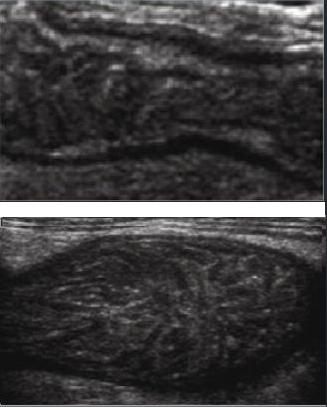

Image echographique

Intestin grele : Image

L'epaisseur de la paroi de

l'intestin normalement est en moyen a 3mm avec des

plies muqueuses et de peristaltisme marquee .

Au ileon la hauteur des plies

muquese est diminue et espace entre des plies

muqueuse sont augementes |

Jejunum : Important de

la presence de plissement de la muqueuse et en

connivence |